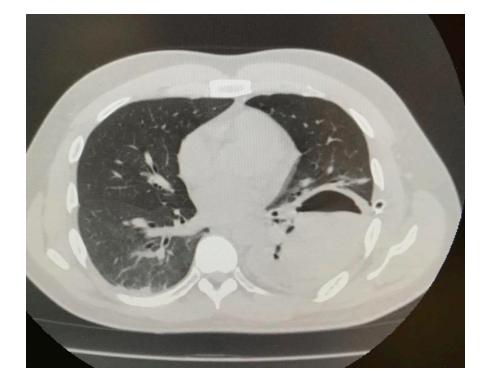

A 33-year-old immunocompetent man brought to the emergency room with symptoms of dry cough, chest pain, and dyspnea for several days and hemoptysis of five days of evolution. His clinical history revealed that he had suffered from pulmonary aspergillosis a month ago without any history of trauma and received treatment with antifungal drug voriconazole for 2 weeks; however, he had poor outpatient follow up of antifungal treatment. His vital signs on admission were as follows: blood pressure 90/50 mmHg, heart rate 114 beats/min, respiratory rate: 18 breaths/min, body temperature 36.3 °C, bodyweight: 190 lbs., height: 5’10’’, and body-mass index 27.2 kg/m2. His physical examination was remarkable for decreased breath sounds on the left hemithorax, otherwise normal examination. Chest radiograph showed a left-sided apical pneumothorax associated with pleural effusion, right mediastinal shifting, and cavitary lesion (Figure 1). Computed tomography (CT) scan of the chest confirmed the presence of a thick-walled cavitary lesion with bronchopleural fistula (Figure 2). Additionally, a complex hemorrhagic left-sided hemopneumothorax linked with the collapse of left lung was detected (Figure 3).

Spontaneous hemopneumothorax is a rare clinical condition resulting from the rupture of tiny blood vessels adhered between parietal and visceral pleura [9]. Bleeding in SHP occurs due to any of the three probable mechanisms- firstly, the rupture of the small non-contractile vessels on the parietal pleura having vascular adhesions with the visceral pleura [1,5,6] secondly, the tearing of vascularized bullae and underlying lung parenchyma and finally, shearing of congenital aberrant blood vessels between the parietal pleura and bullae [1,4-6]. The resulting hemorrhage and shock may require emergency surgery [7]. SHP is a complication of primary or secondary pneumothorax [5]. The chest Xray of our patient revealed a left-sided apical pneumothorax associated with pleural effusion indicating the link between spontaneous pneumothorax with SHP in the absence of any trauma, underlying lung diseases, and surgery. Pleural effusion is directly correlated to pleural invasion and has a high hematocrit value and bloody appearance [10].